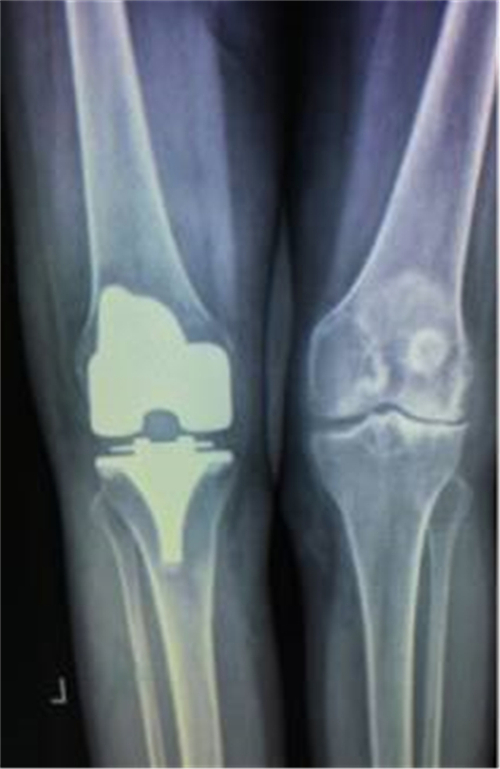

得知郴州市第四人民医院骨科掌握了这一手术技术,便前来就诊。谭主任接诊到该患者后,对其进行了详细的体格检查,发现其左膝关节僵直,屈伸活动不能,负重时膝关节疼痛明显加重,膝关节X线片提示膝关节退变严重,关节间隙明显变窄,并有游离体形成,诊断为左膝关节重度骨关节炎并关节僵直,有明确的膝关节置换手术指征。

术前X线

术后X线